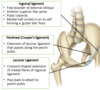

Label this image

Label this image

Label this image